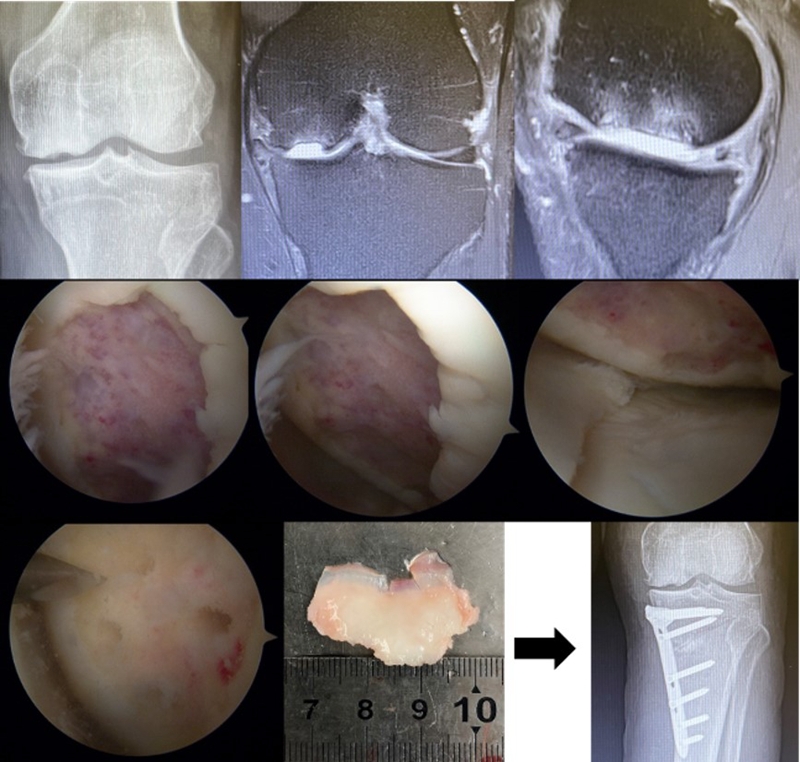

病例1:女,61岁,右膝关节诊断为Koshino Ⅲ期SONK,行右膝内侧单髁手术治疗。

病例1:男,64岁,主诉左膝关节内侧疼痛6年余。MR提示骨坏死区占比为33.28%,矢状位病变区域前后径为26.42mm,半月板相对突出百分比(RPE)31.78%,同时存在胫骨侧来源的下肢内翻畸形(MPTA83°),关节线会聚角2°。

行关节镜检查+软骨摘除+微骨折+HTO术,术后随访2年恢复良好,活动自如,行走时无左膝关节疼痛不适。

病例2:女,81岁,行内侧单髁手术治疗,术后恢复良好。